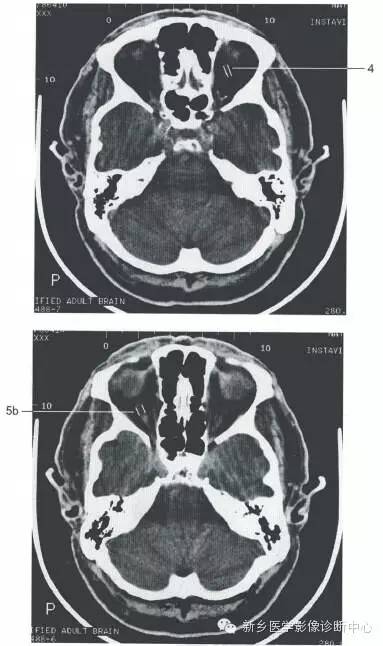

颅脑大体及磁共振断层解剖